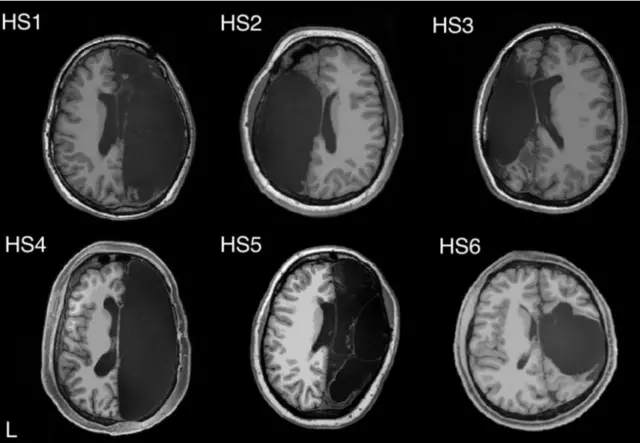

ทีมผู้วิจัยสันนิษฐานว่า การปรับตัวของสมองส่วนที่เหลืออยู่ของคนไข้เหล่านี้ น่าจะมีความเกี่ยวข้องกับเรื่องน่าประหลาดใจดังกล่าว จึงมีการทดลองให้ผู้ที่เคยผ่านการผ่าตัดเอาเนื้อสมองออกซีกหนึ่งในวัยเด็ก 6 ราย เข้ารับการตรวจสมองด้วยเครื่องสแกน MRI และเปรียบเทียบข้อมูลที่ได้กับกลุ่มควบคุมซึ่งมีสมองสมบูรณ์ตามปกติ รวมทั้งเปรียบเทียบกับฐานข้อมูลผลสแกนสมองของชาวอเมริกัน 1,482 คนด้วย

ที่มาของภาพ, CALTECH